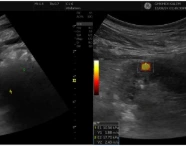

Postpartum Haemorrhage: A Case Series Highlighting Diverse Clinical Profiles and Evolving Management Strategies in a Tertiary Care Setting